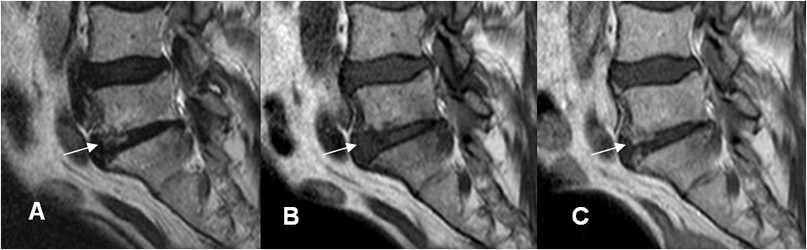

Fig 141 B. Diferencial de espondilodisquitis.

A: RM sagital en T1, B: RM sagital en T2 y C: RM sagital en STIR. Cambios inflamatorios en las placas terminales de L5-S1, Las cuales son hipointensas en T1 e hiperintensas en T2 y STIR. (Flechas).

Fig 141 C. Diferencial de espondilodisquitis. Igual paciente anterior.

A: RM sagital en T2, B: RM sagital en T1 simple y C: RM sagital en T1 con contraste.

Cambios inflamatorios en la porción anterior del disco, siendo hiperintensa en T2 y con realce del contraste, por espondilodisquitis.